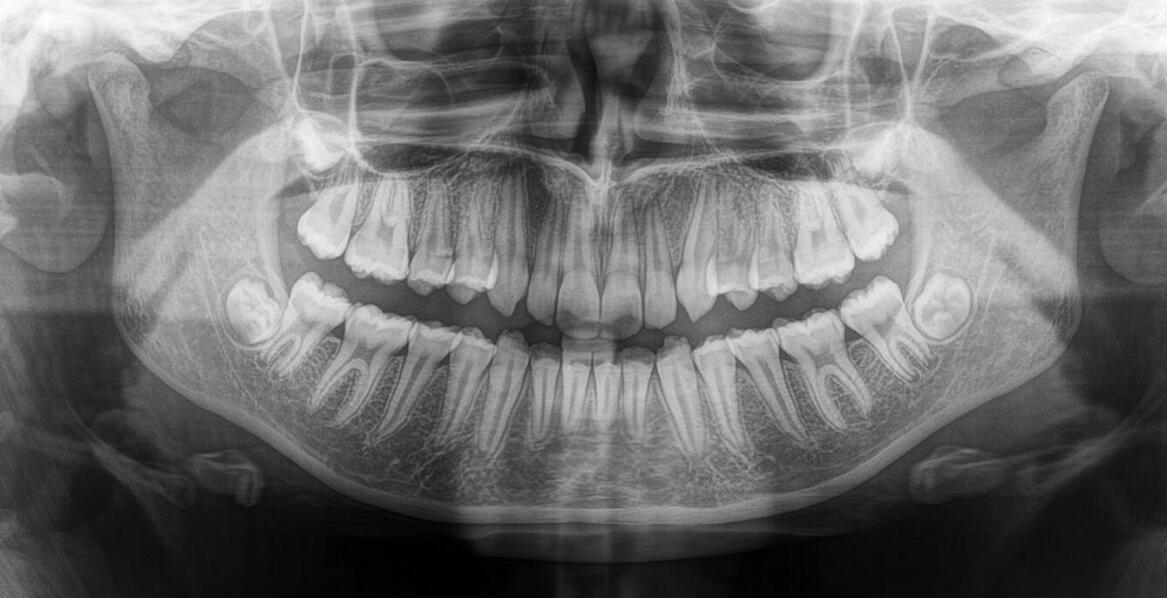

Zdjęcie panoramiczne zębów to istotny element diagnostyki stomatologicznej, umożliwiający uzyskanie dokładnych obrazów jamy ustnej. Warto wykonać to badanie, ponieważ pozwala na identyfikację problemów stomatologicznych, takich jak próchnica czy choroby przyzębia, oraz ocenę stanu zębów i kości prze